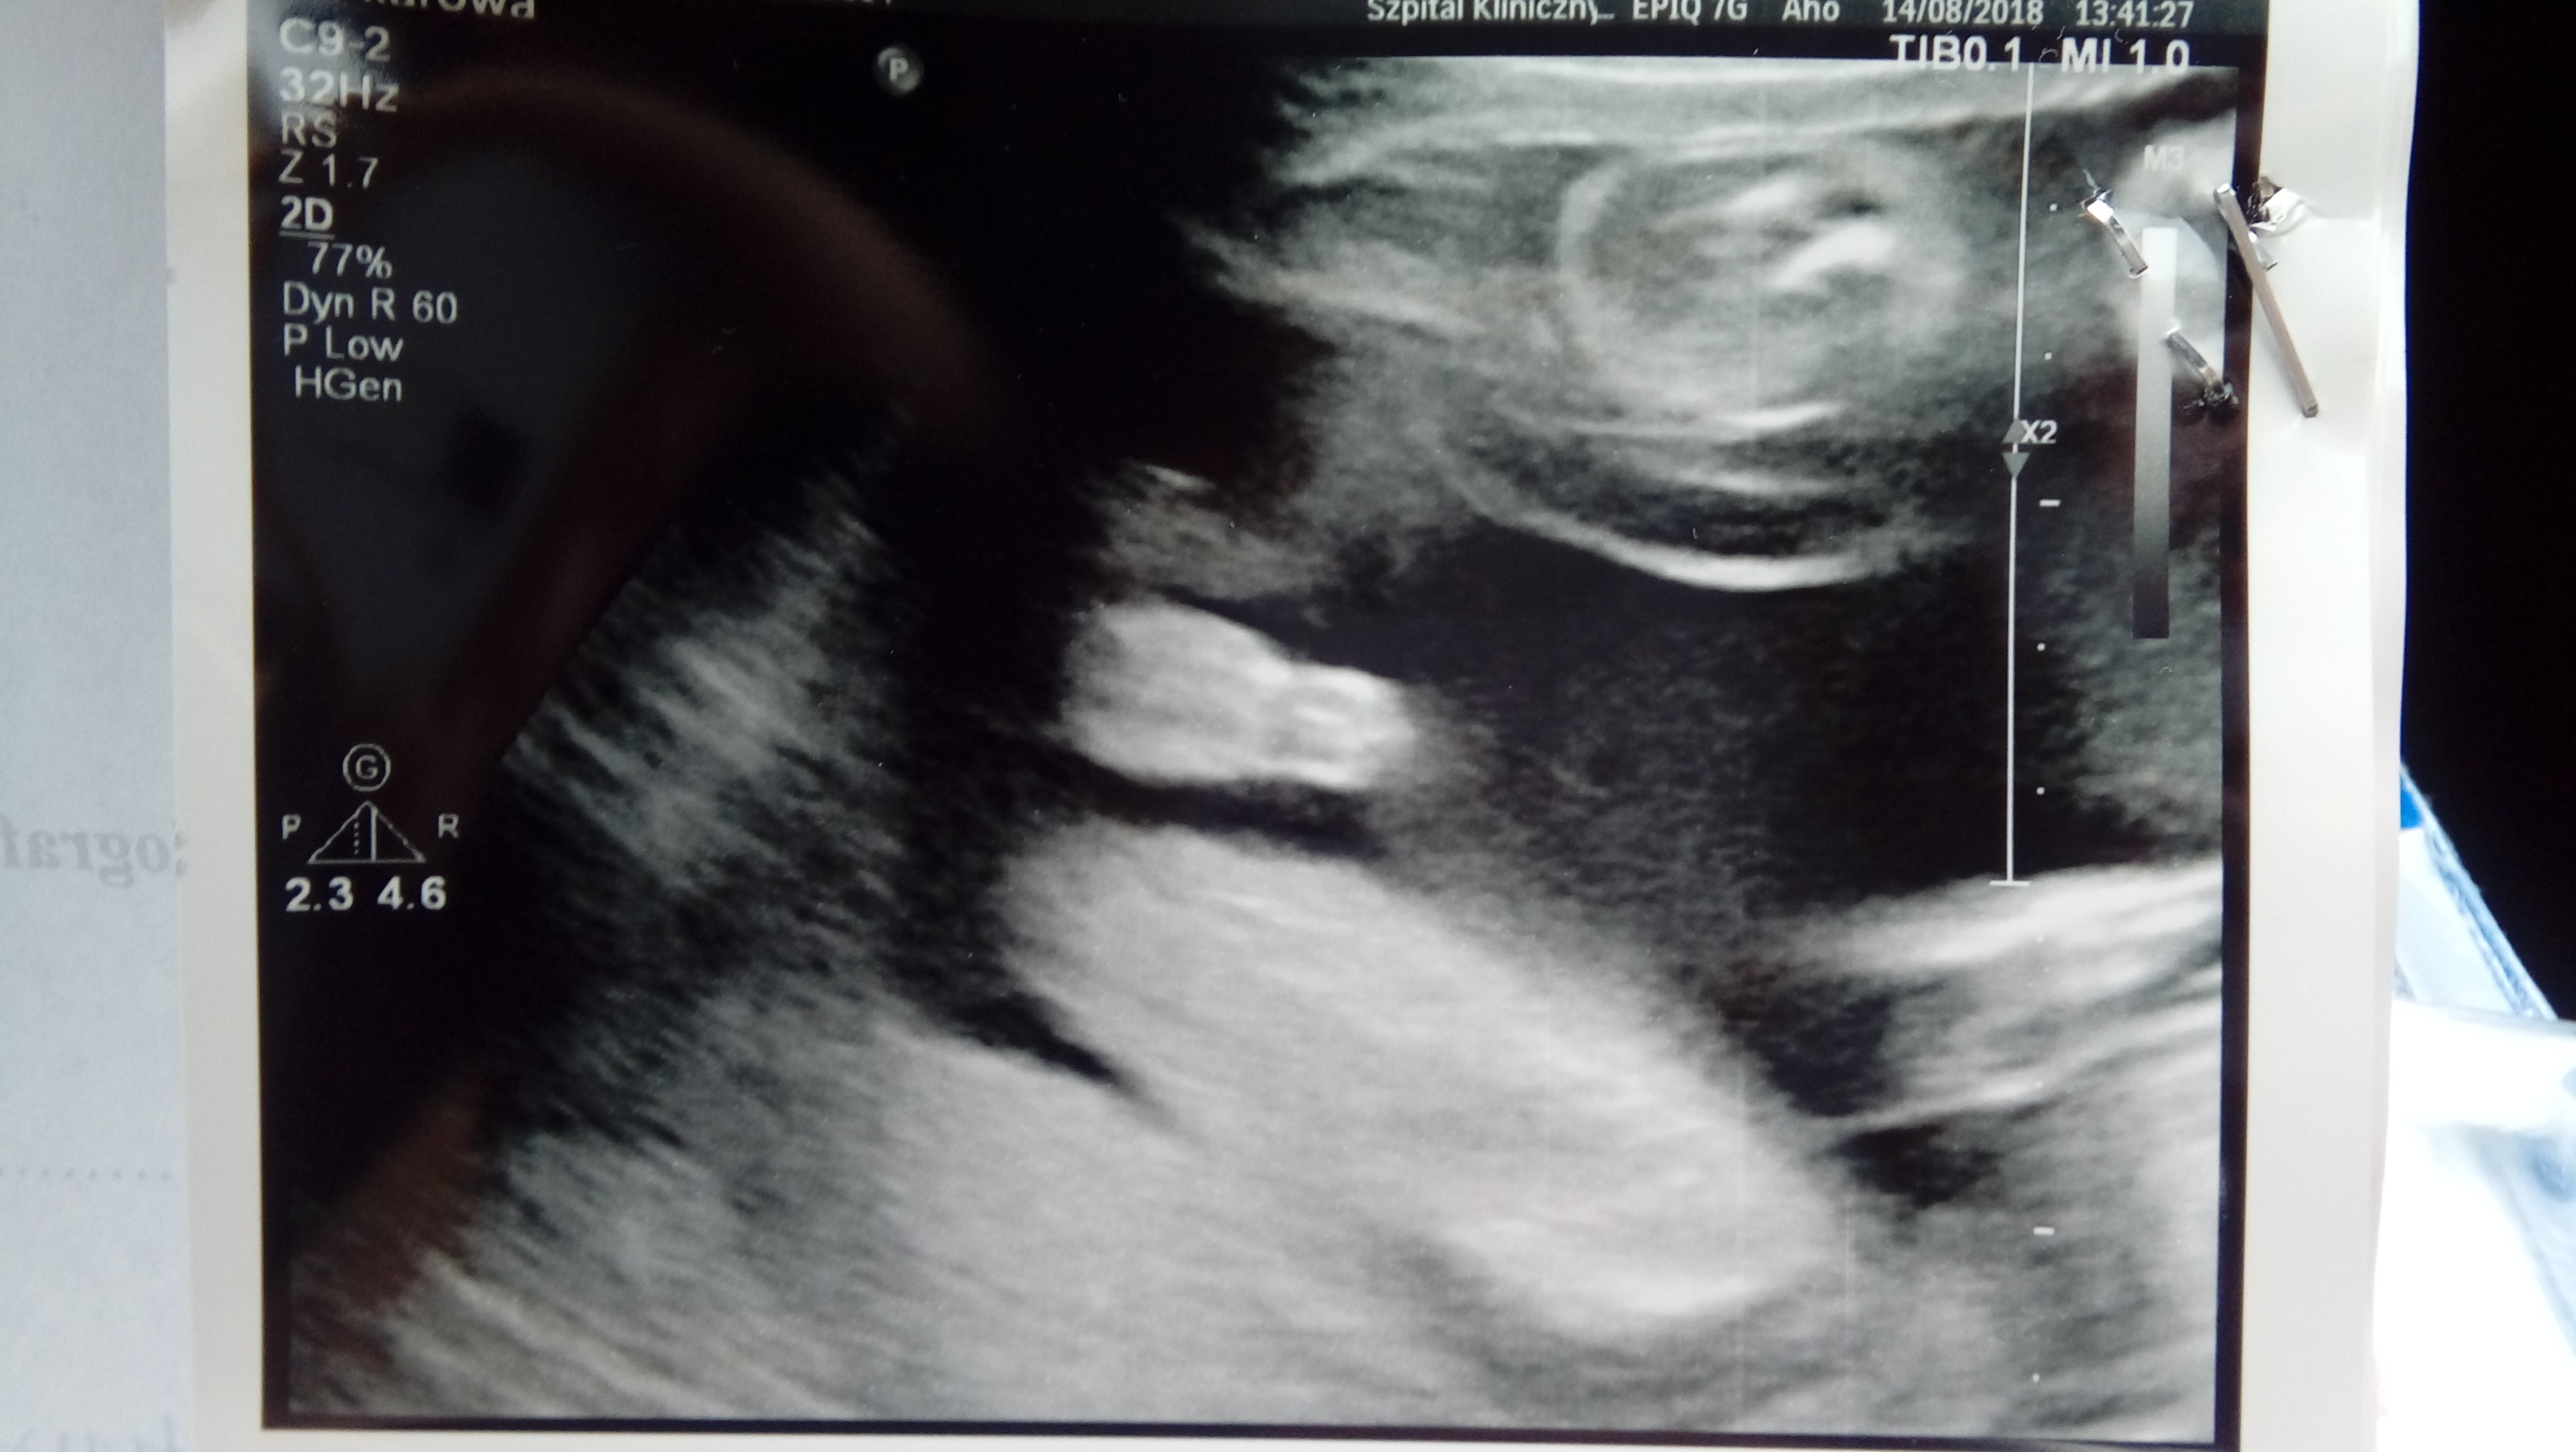

Czasem boję się, że się obudzę z tego snu, bo tylko na usg i potem na tych zdjęciach widzę, że to prawda.

Ja wczoraj mialam ostatnie badanie serduszka babelka:) skonczony 24 tc i ponoc juz nie ma ryzyka:) dr mowi ze tak jest z jej doświadczenia . dostalam piekne zdjecie siurasa i malo wyrazne ale jest jak ssie malenstwo kciuk.

Załączniki

• 20180814_141110-1.jpg

20180814_141110-1.jpg

405 KB · Wyświetleń: 96